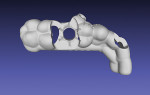

Before the implant was placed a provisional crown was designed and prefabricated using a digital workflow (CARES Visual). The provisional crown was milled in polymethyl methacrylate (PMMA) (Vita CAD-Temp® monoColor, VITA, vitanorthamerica.com) using a milling unit (Straumann® M Series, Straumann).

The patient was re-evaluated after an additional 3 weeks of healing (5 weeks total). The peri-implant soft tissues were in excellent health and the patient reported no concerns. The provisional restoration was removed and the soft tissue evaluated (Figure 16). A scanbody (CARES® Mono Scanbody, Straumann) was positioned and a final digital impression was captured with an intraoral scanner (Virtuo Vivo). The intraoral scans and virtual articulation records were imported in a CAD/CAM software program (CARES Visual), which was used to design the definitive zirconia crown. The definitive crown was designed for luting to a titanium abutment (Variobase® for Crown, Straumann) prior to delivery (Figure 17), enabling screw retention of the definitive prosthesis at the level of the implant.